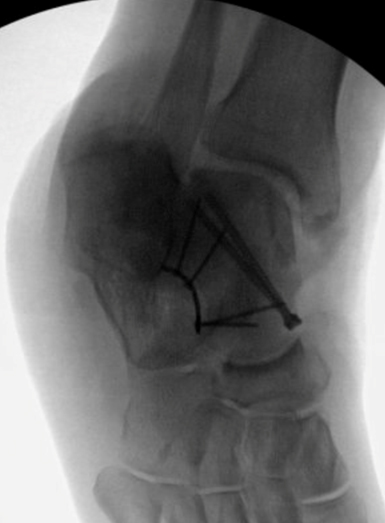

TOTAL ANKLE REPLACEMENT :: ORIF CALCANEUS :: ORIF ANKLE FRACTURE DISLOCATION :: COMPLEX BUNION AND LESSER TOE CORRECTION :: TALUS FRACTURE -1 :: TALUS FRACTURE -2 :: LISFRANC REPAIR :: COMPLEX TRIPLE ARTHRODESIS 1 :: COMPLEX TRIPLE ARTHRODESIS 2 :: MINIMALLY INVASIVE BUNION REPAIR 1 :: MINIMALLY INVASIVE BUNION REPAIR 2 :: ARTHROSCOPIC CARTILAGE REPAIR :: TENEX SPUR DEBRIDEMENT :: Haglunds Debridement and Achilles Repair